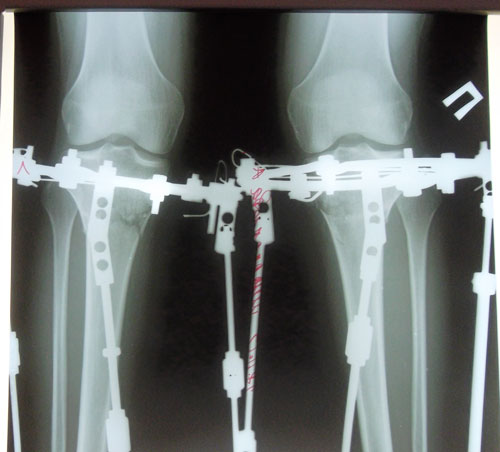

Ножки на 41-й день с момента операции.